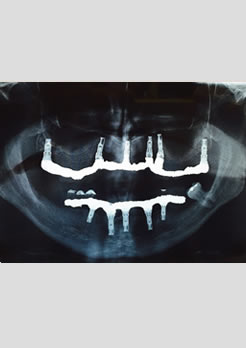

Paciente sexo masculino 62 anos, portando dentadura superior e vários dentes inferiores comprometidos. Foi indicado duas prótese fixas aparafusadas, na arcada supeior foram realizados 6 implantes e na arcada inferior 5 implantes.

RX panorâmico após a instalação das próteses